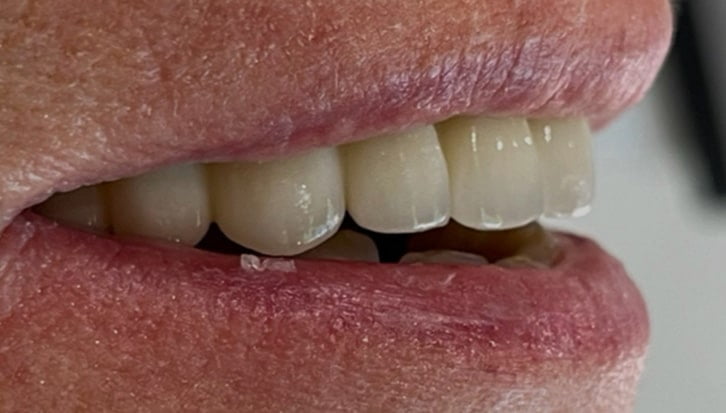

Dental Implant Cases

Aberdeen Implant Centre

Beautiful new smiles created at the Dental implant centre